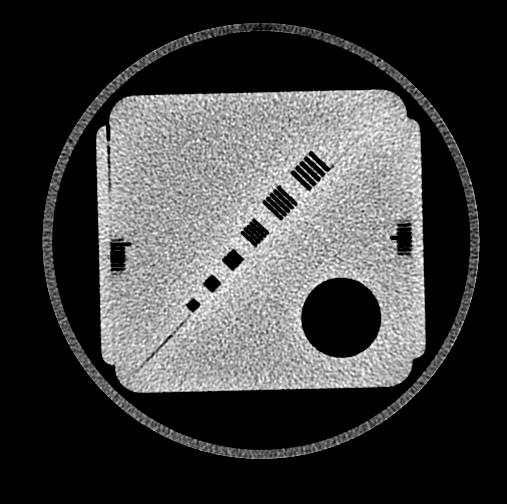

Automated Phantom QC

is available for the ACR and vendor phantoms.

Automated Phantom Analysis

provides a fast, flexible, and consistent method to extract and process phantom and DICOM data and automatically insert the data into QC-Track worksheets.